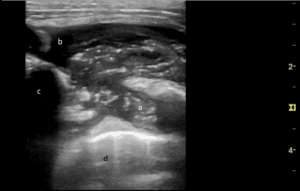

Figure 3. Soft tissue ultrasound image showing an enlarged right supraclavicular lymph node.

He was subsequently referred to pulmonary medicine for endobronchial ultrasound (EBUS) and transbronchial needle aspiration (TBNA) for both diagnostic and staging purposes. However, his scans were reviewed and notable for an enlarged right-sided supraclavicular lymph node, which was not palpable on exam (Figure 2). A point of care ultrasound (POCUS) assessment of his right supraclavicular region with a linear probe demonstrated the findings in Figure 3 and Videos S1 and S2. Based on the patient’s clinical history and findings from the images and videos, we proceeded with ultrasound-guided fine needle aspiration (FNA). This provided a diagnosis of lung cancer and provided staging in a safer and less invasive way than EBUS.

Practically, suspicious neck lymph nodes are identified using a linear transducer. Lymph nodes are characterized as echodense structures surrounded by a clearly defined hyperechoic capsule that are not collapsible, may have a fatty central hilum, and do not show evidence of blood flow on color or spectral Doppler [5]. Once location is confirmed, the site is cleaned, a local anesthetic is applied, and if needed, additional sedation mirroring other routine subcutaneous procedures is provided. In our practice, sampling of the identified lymph is done under real-time ultrasound guidance and an in-plane needle approach with 3-5 passes using an 18, 21, or 22 gauge needle and 10 cc syringe assembled in a needle gun (Figure 4, Video S3). This is akin to a version of the traditional view seen with EBUS-TBNA sampling. Each pass is evaluated with rapid on-site examination by the cytopathology team in the procedure room.